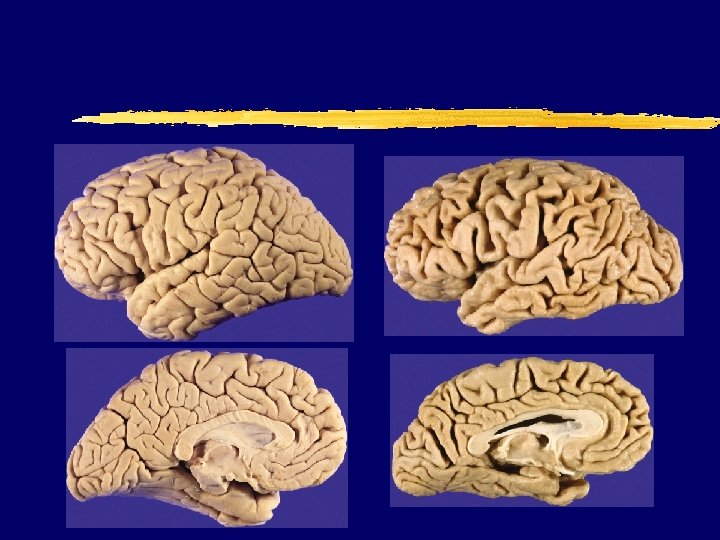

Normal (73 y. ) vs. AD brain (73 y. )